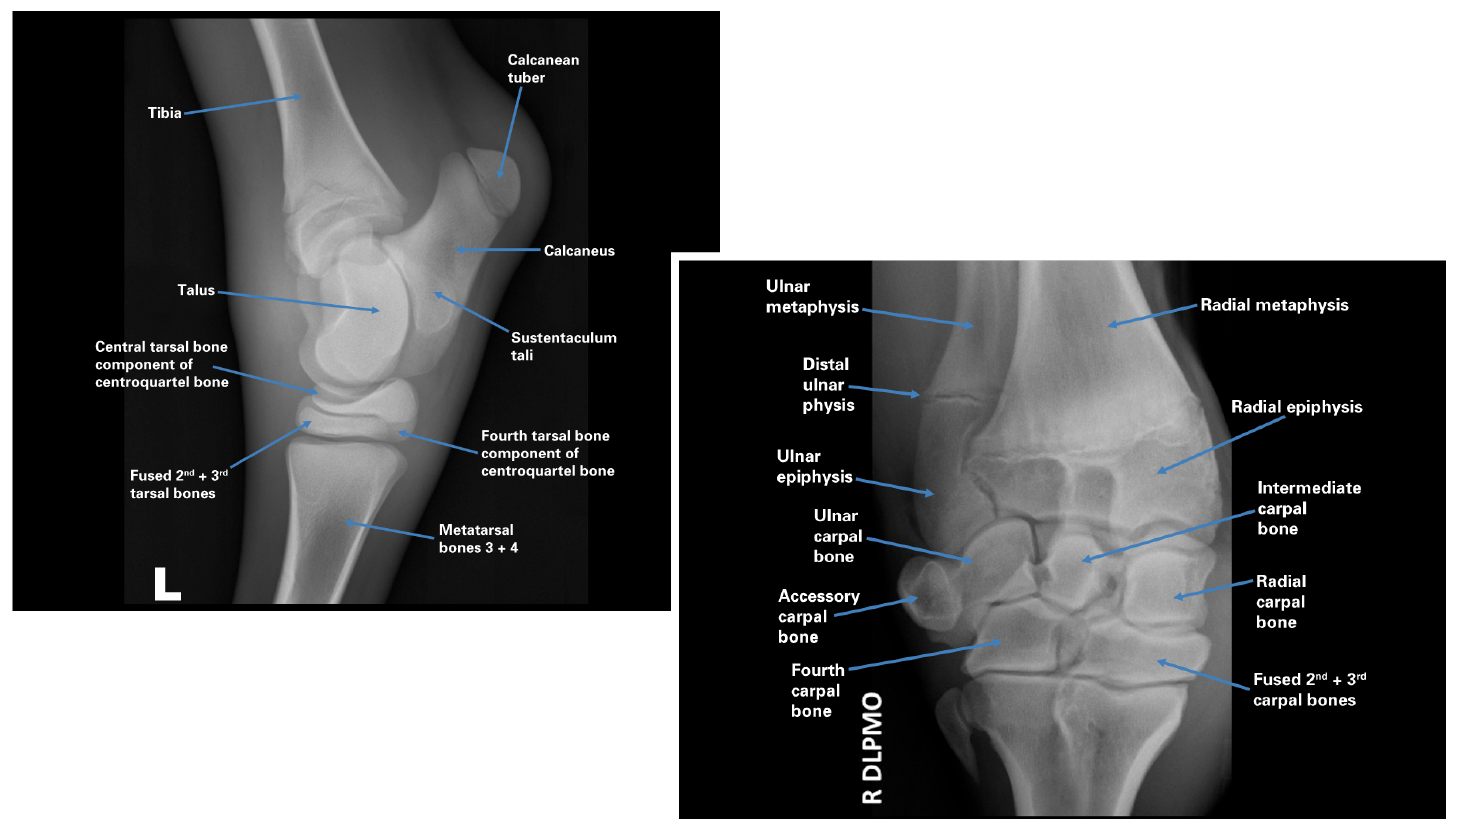

It is the most complete reference of human explore over 6700 anatomic structures and more than 670 000 translated medical labels. Anatomies like brain, temporal bone/internal auditory meatus, nasopharynx, orbit, paranasal we hope you enjoy our online interactive service by clicking on the following anatomical parts Fast & comprehensive ct cross sectional human anatomy interactive medical imaging atlas for ios, for medical professionals & students.